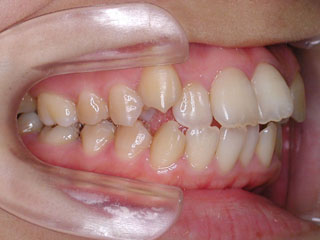

過蓋咬合が見られます。下顎の前歯がほとんど見えない状態に隠れています。タイプとしては2級2類と呼ばれる不正咬合です。上下共に中程度以上の叢生が見られますが、上顎前突の改善のために上顎のみ小臼歯抜歯としました。

使用した主な装置名:HG、TPB、マルチブラケット装置

抜歯/非抜歯および抜歯部位:抜歯(上顎左右第一小臼歯)

治療期間:動的処置1年10か月、経過観察3年